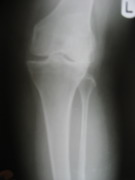

Knee Joint Replacement